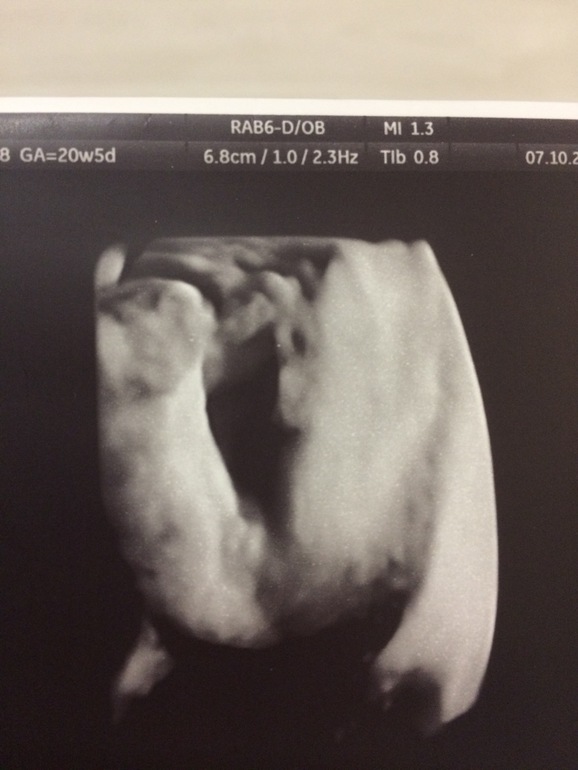

Все у Малышки хорошо, пол с 12 недели не изменился. Фото пирожочка нашего сделали, как доказательство ))))